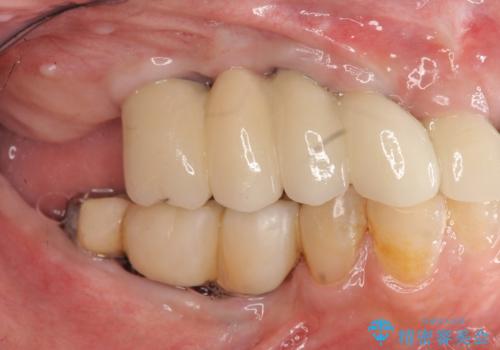

他院で中途半端に終わってしまったインプラント治療

- 他院で1本インプラントを入れたまま治療に通うことができなくなり、途中からの治療を希望され来院されました。

既に埋入されているインプラントは位置が悪いのでそのまま骨内に留置することとし、新たに咬合機能を回復すべく3本のインプラントを埋入すると同時に吸収した骨幅を増やし、安定してインプラントで噛める環境整備を目指します。

インプラントが長持ちするために、インプラント周囲の十分な骨量・角化歯肉の存在・安定した咬合を一つづつ整備する治療を行いました。